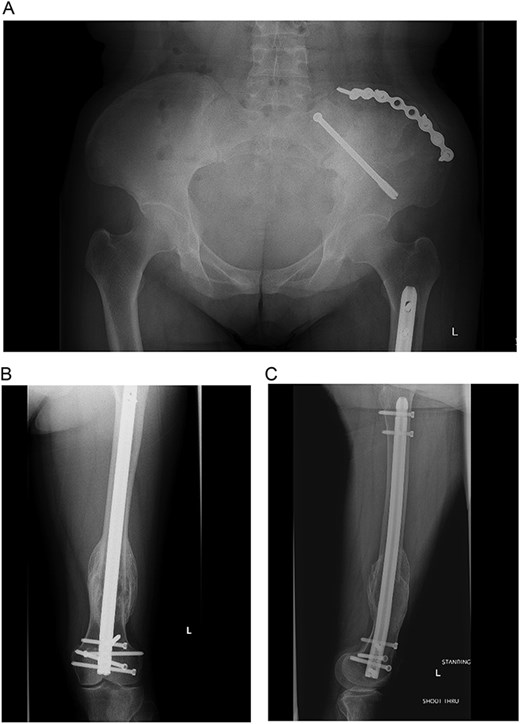

(A–C) Final radiographs showing complete healing >1 year postoperatively.